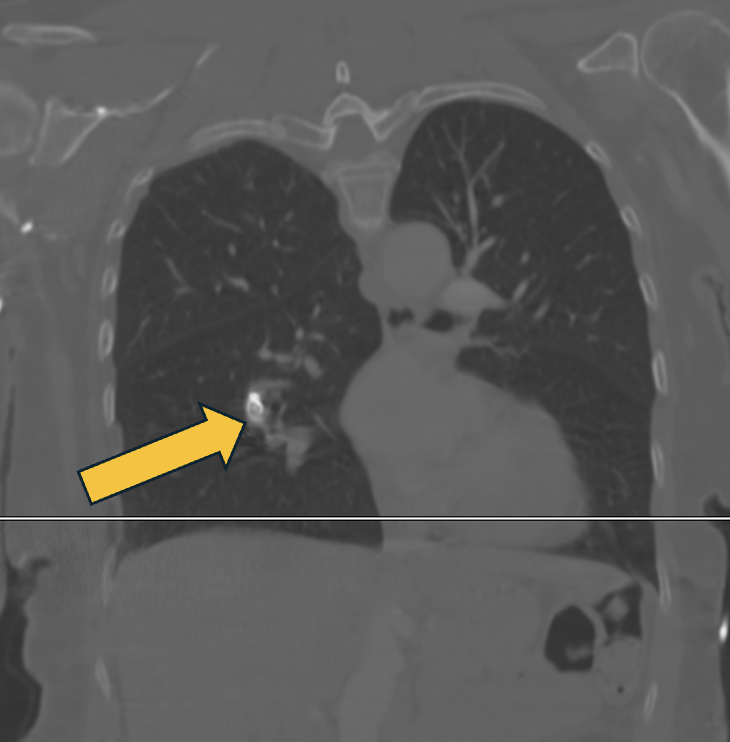

A 29-year-old woman with a history of exertional dyspnea undergoes a cardiac CT for evaluation of suspected congenital heart disease. What is the underlying congenital anomaly demonstrated? #Cardiology #Radiology #MedEd #MedTwitter

When the incidental finding is actually the life-threatening one...what is the finding?? 🫁⚠️ #medstudent #cardiologist #heart #medical #medicine